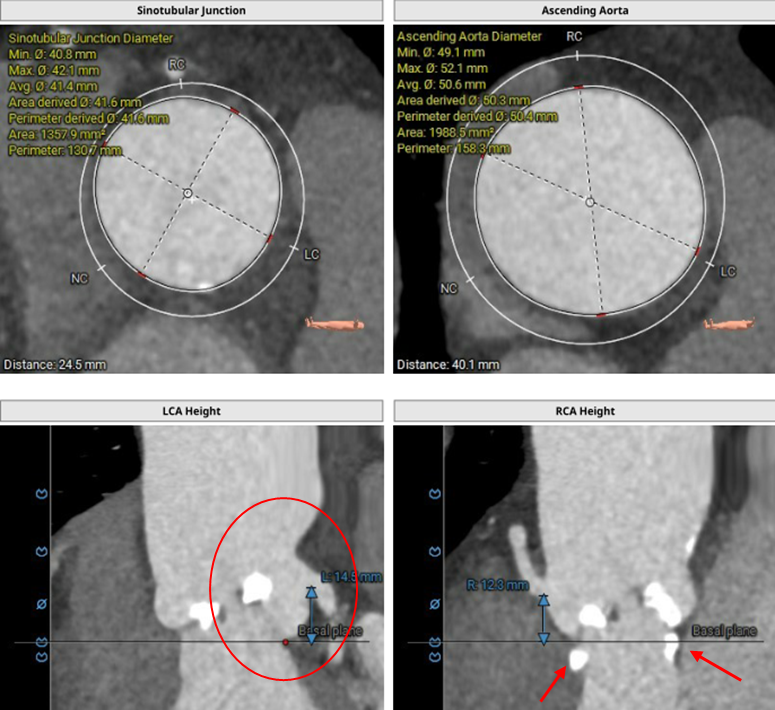

术前CT评估:

CT测量小结:

主动脉瓣为type -I 型二叶瓣,右无瓣叶嵴部融合伴有钙化并向窦部延伸16.0mm,瓣环平面可见钙化斑块向左室流出道延伸约12.3mm,瓣叶极重度钙化,中重度增厚;左冠窦较右无冠窦略偏大,右无冠窦基本等大;右冠脉开口高度可,左冠脉开口处可见瓣叶钙化斑块;心室大小可,室壁厚度可,中重度横位心;大血管走行自然,内径可,升主动脉扩张,主动脉弓部角度可,弓部、降主、腹主、左髂总动脉可见少-中量钙化斑块。